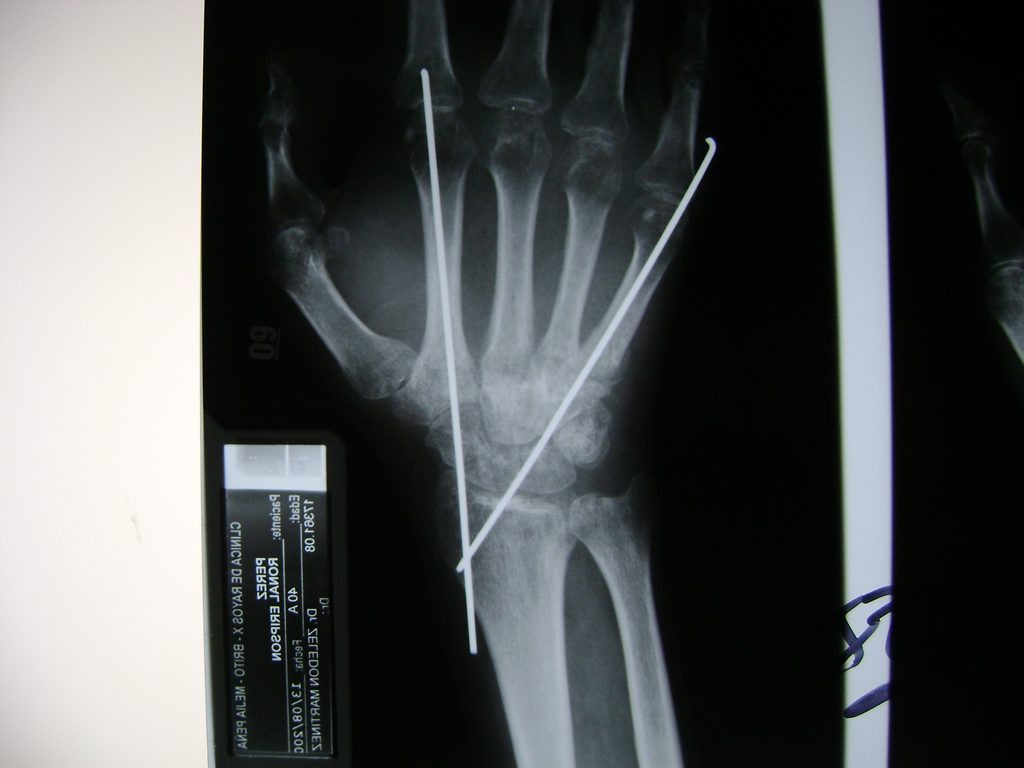

Los procedimientos más comunes en cirugía de la mano son aquellos destinados a reparar traumatismos, incluyendo lesiones de tendones, nervios, vasos sanguíneos, y articulaciones; huesos fracturados; y quemaduras, cortes, y otros daños de la piel.